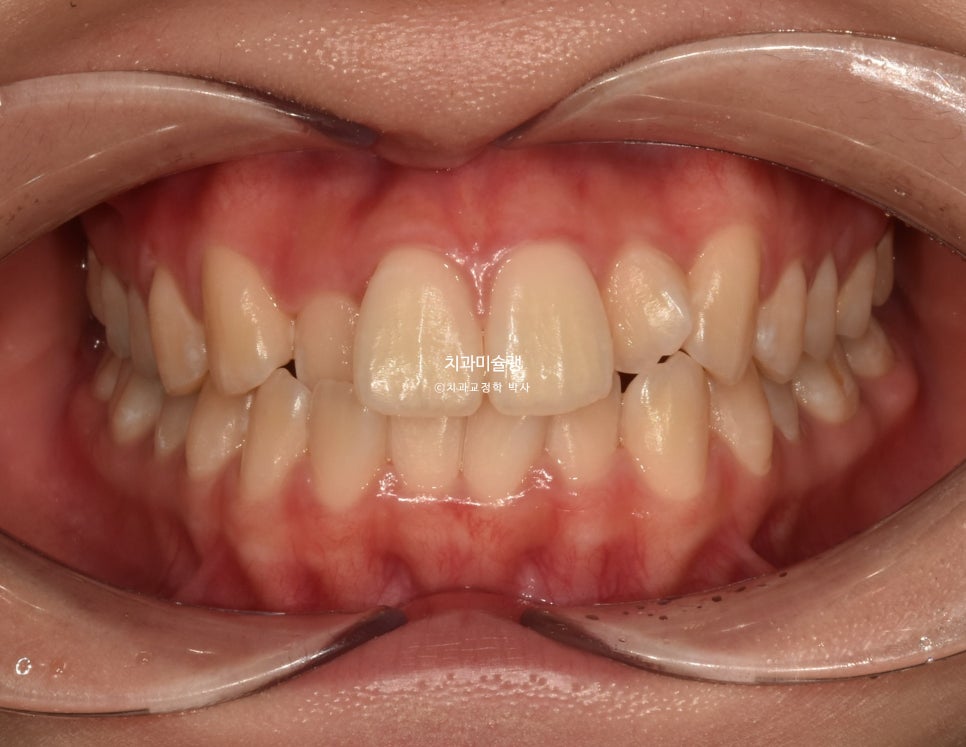

24년 8월 교정치료를 위해 온 환자분입니다. 고치고 싶은것은 돌출, 배열.

측절치가 입천장 쪽으로 들어가 있어 반대교합이 보이며 중심선 불일치가 보입니다.

어금니 교합은 1급으로 좋습니다.

마침 사랑니를 다 뺀 상태인데다 사랑니 공간도 충분하여

작은어금니는 보존하고 사랑니 공간을 이용하기로 합니다.

환자분은 작은어금니 발치를 원치 않았기도 하고 입술돌출이 뚜렷하지 않기 때문에 비발치교정으로 치료계획을 세웁니다. 이를 위해 교정용 미니스크류는 필수입니다. 큰 앞니 사이즈를 줄이기 위해 치간삭제도 함께 계획했습니다.